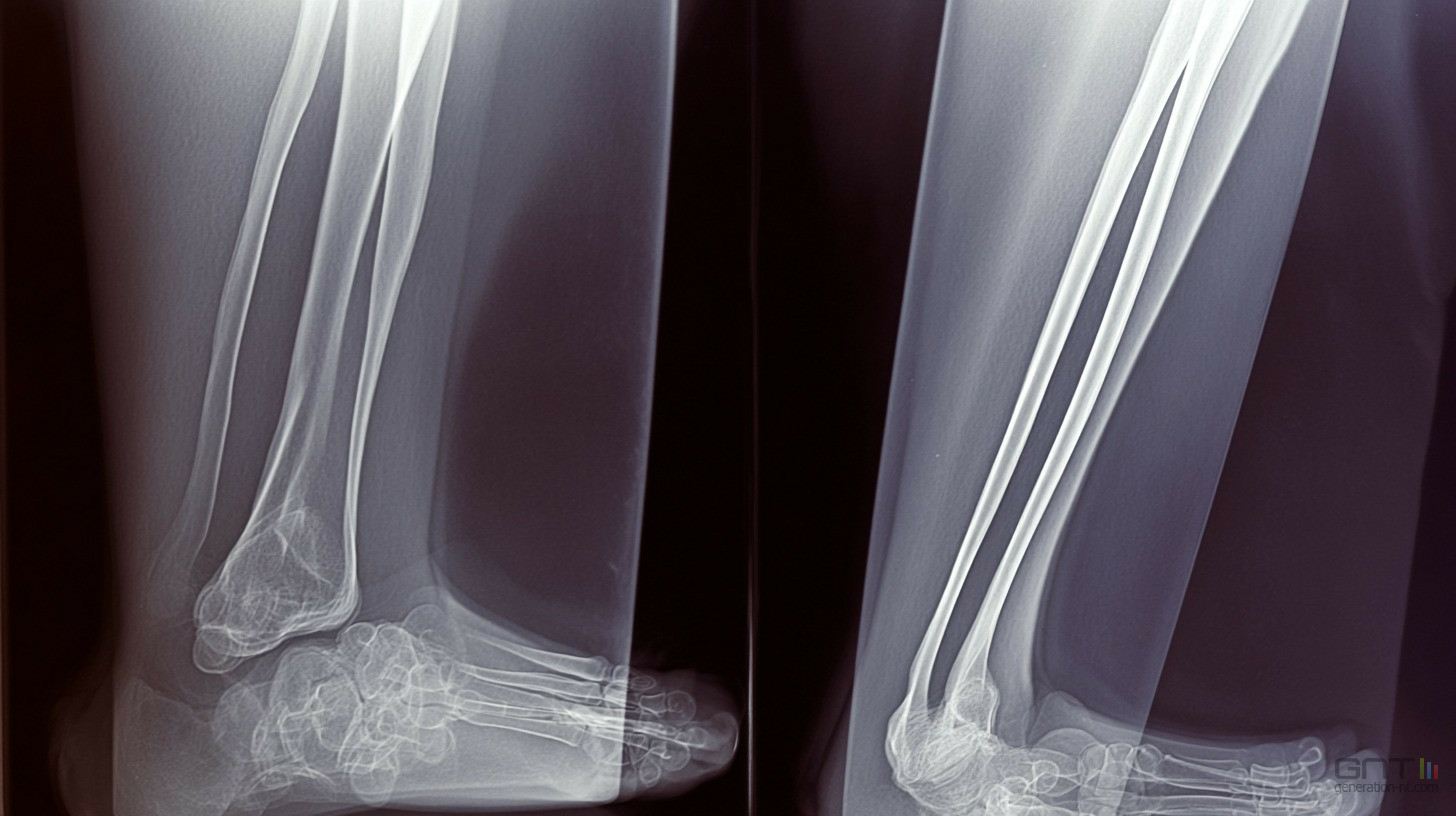

Ce n'est que le début d'une transformation profonde. Si l'accent est mis aujourd'hui sur la traumatologie osseuse, les hôpitaux envisagent déjà l'étape suivante avec beaucoup d'intérêt. Le groupe de travail régional sur l'imagerie médicale explore l'utilisation de ces technologies pour les radiographies thoraciques ou même la détection précoce de cancers.

L'objectif à long terme est de fluidifier l'ensemble du parcours de soin, bien au-delà de la simple analyse d'une cheville foulée. On se dirige vers une médecine augmentée, plus rapide et plus sûre pour tout le monde.